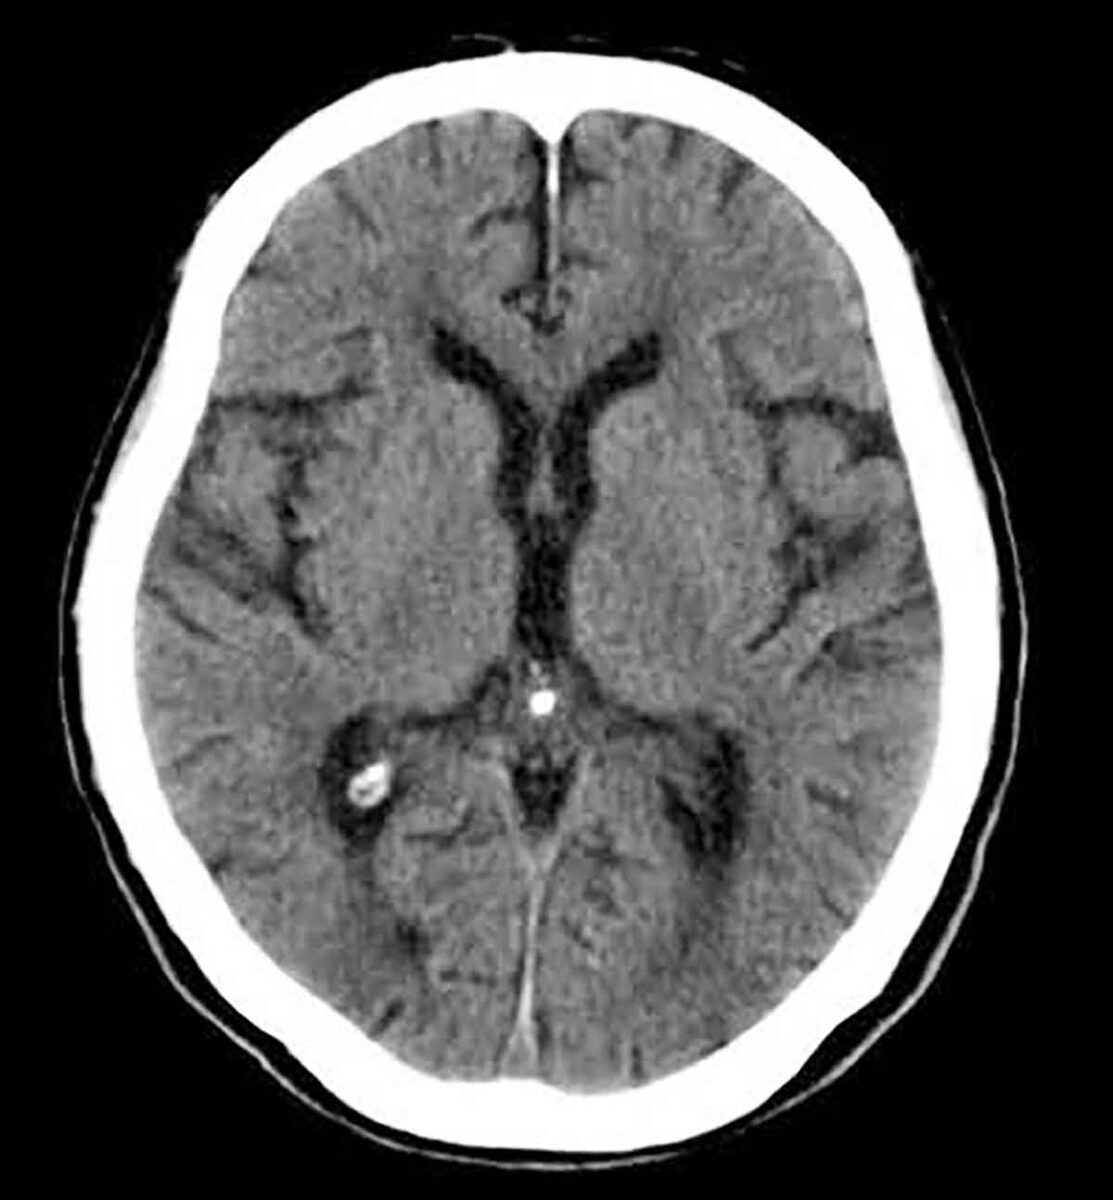

3. Exame complementar obrigatório, como eletroencefalograma (que identifica atividade elétrica cerebral), Doppler transcraniano (que avalia fluxo sanguíneo cerebral), cintilografia ou arteriografia cerebral. Todos têm como objetivo comprovar, por vias técnicas, que não há mais funcionamento cerebral.

Esses exames devem ser realizados com intervalo mínimo de tempo entre as avaliações, respeitando a idade do paciente e as normas da resolução. Só após a conclusão de todas essas etapas é emitido o Termo de Declaração de Morte Encefálica, documento legal que atesta o óbito.